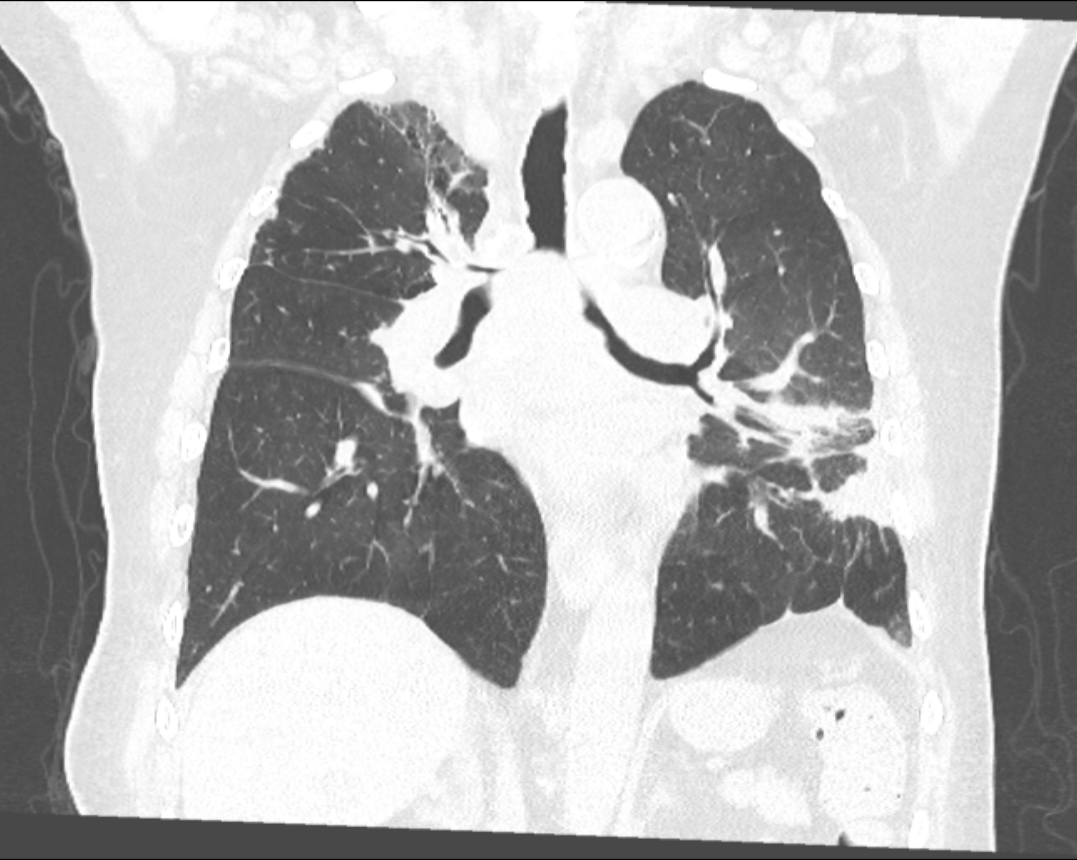

患者术前CT

患者支架置入后CT

呼吸与危重症医学科常务副主任、呼吸介入专业组组长王峰对患者进行CT扫描和相关检查。结果显示,患者呼吸困难症状加剧是由于肺部巨大肿瘤压迫气管下段、隆突以及左右主支气管所致。由于气管狭窄的位置特殊,影响到主气管及两侧的主支气管。经过呼吸介入团队的仔细评估,并与麻醉科多次协商,以及与患者及其家属的充分沟通,最终决定采用硬镜联合柔性支气管镜引导的方式,为患者植入“Y型金属覆膜支架”,以重新开通气道,缓解呼吸困难的症状,并为后续的抗肿瘤治疗争取宝贵时间。

手术过程中,王峰带领呼吸介入团队与麻醉团队紧密协作,运用精湛的硬质气管镜操作技巧,根据术前的精准评估,顺利完成导丝放置、精准定位、支架释放及位置调整等一系列操作。在有限的镇静麻醉条件下,成功地将“Y型气管覆膜支架”置入患者体内,显著改善患者气管下段以及左右主支气管的狭窄状况。术后,患者的喘息、胸闷和气短等症状得到明显缓解。